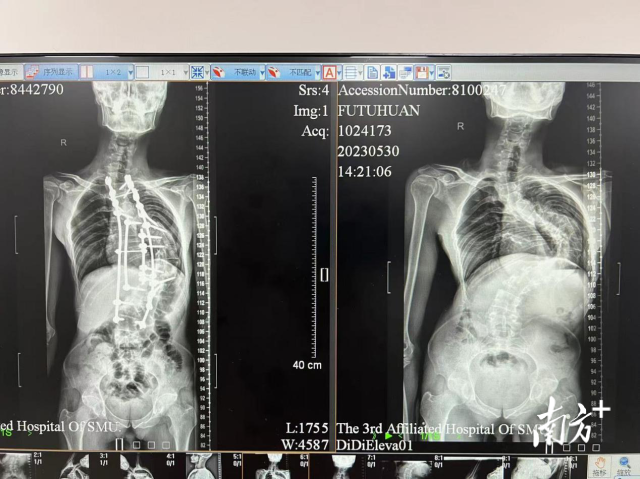

手术前后对比(右为手术前)

其次,由于很小就发病了,但一直没有治疗,病史较长,吴先生脊柱侧弯的角度随着年龄的增长不断加大,已形成了一个“问号”形状的弯曲。这让他的背部顶出一个大包,不仅难看,还导致吴先生躯干短缩,个子变得越来越矮小,头也抬不起来了。

如今,吴先生弯曲的背直了,后凸的大包变得平整,脊柱被矫正拉直,还长高了10厘米。挺胸抬头的他说,最大的遗憾是没有早一点寻求治疗,被病痛折磨了整个青春。